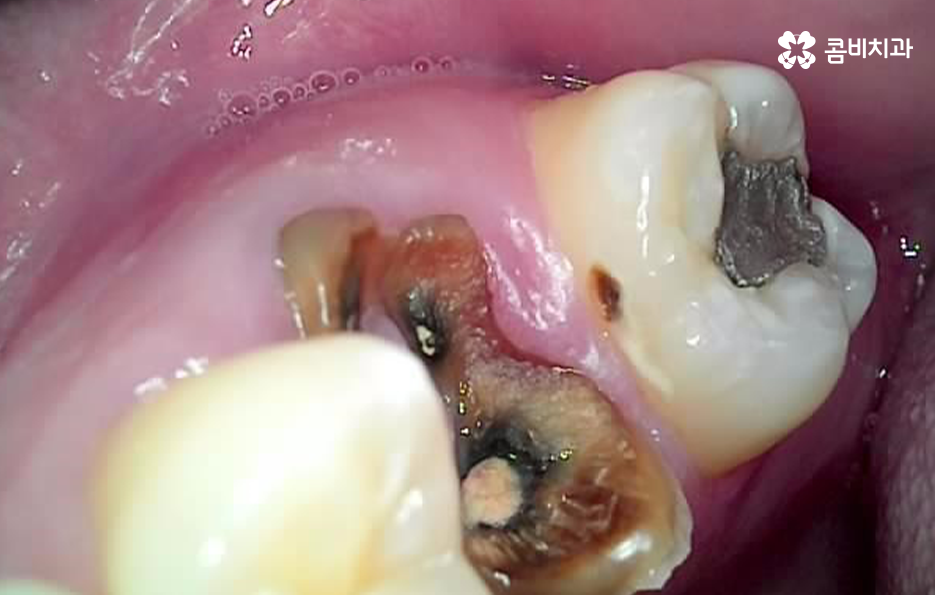

뿌리 끝에 발생한 염증의 경우 불편함을 못느끼더라도 빨리 치료하는 것이 좋은 이유는 시간이 지날수록 작았던 염증은 점점 커지게 되고 잇몸 뼈를 녹게 만들어 치아가 결국 흔들리게 될 수 있고, 당장 통증이 없더라도 치료 시기를 놓쳐, 일정 수준 이상으로 진행이 된 경우 급성치수염 증상으로 진통제를 먹어도 통증이 잡히지 않을 정도로 극심한 통증이 동반될 수 있습니다.

잇몸 뼈에 문제가 생겨 치아가 흔들리게 되면 보통 치료의 골든타임을 놓치게 되기 때문에 이때는 신경치료를 시도할 수도 없고, 치근단절제술이나 치아재식술을 시도해 볼 수 있지만, 성공 확률이 높지 않기 때문에 치아를 발치해야 하는 경우가 대부분이라고 할 수 있어요

충치에 대해서는 환자분들께서 대부분 빨리 치료하는 것이 중요하고 그냥 둔다고 해결되지 않는다는 것을 잘 알기 때문에 치과 검진을 통해 발견되면 대부분 치료를 잘 받고 가시지만 불편한 증상이 크지 않은 경우에는 문제의 인지 자체가 늦어져서 치료의 적기를 놓치는 경우가 많이 있는데요

자연치아를 최대한 잘 보존하고 문제가 발생하더라도 초기에 잘 치료하기 위해서는 주기적으로 검진과 스케일링을 잘 받는 것이 가장 기본이자 중요하다고 강조 드리고 있어요